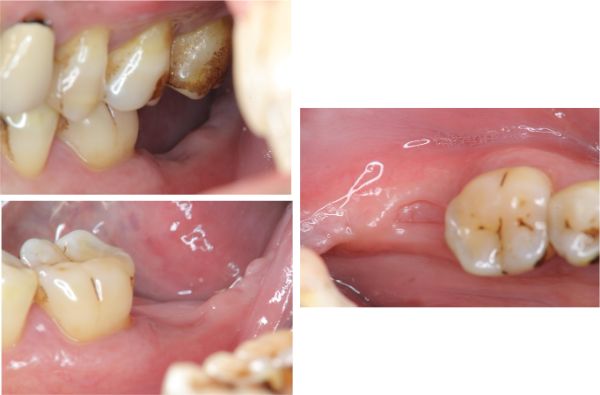

拔牙補骨

6個月追蹤

骨癒合良好